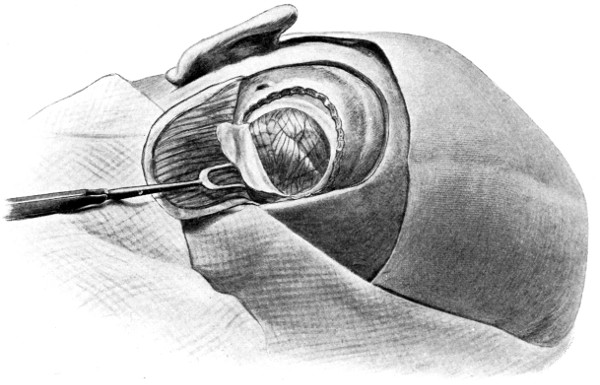

Between these two trephine-holes the dura mater is separated from the bone and the special director introduced, entering at the one hole, emerging at the other, and lying throughout between the dura and the bone. The saw is now passed along the groove of the director, the handles affixed, and the bone intervening between the two trephine-holes divided, not straight out to the surface, but bevelled or cut in such an oblique manner that the bone-flap, when replaced, rests on a ledge (see Figs. 17-19). The sawing process[26] generates considerable heat, and the assistant should be instructed to keep up irrigation with saline solution or sterilized water. The sawing is carried out by steady side-to-side traction, without jerks; if the saw breaks, the special handle may be attached, thus obviating the necessity of introducing a new saw.

Fig. 17. First Stage in the Formation of an Osteoplastic Flap. Gigli’s saw, protected from the dura mater by the special director, passing between the two trephine-holes. For further description, see text.